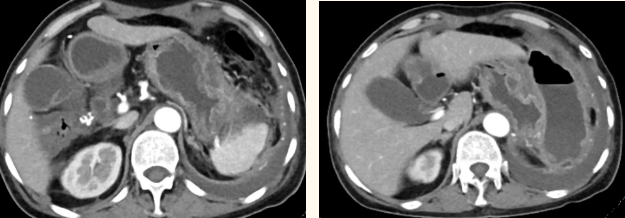

一籌莫展的她終于在病友的介紹下,來到西安國際醫(yī)學中心醫(yī)院找到蔡磊主任。經(jīng)過詢問病史,查體等,蔡磊主任建議口服索坦治療。3個月后,李阿姨復查CT提示胃間質瘤較前明顯縮小,大小約10.4cm?6cm。但仍存在消化道出血,營養(yǎng)狀況差,全身無力,骨髓抑制。蔡磊主任隨即將患者收治入院。